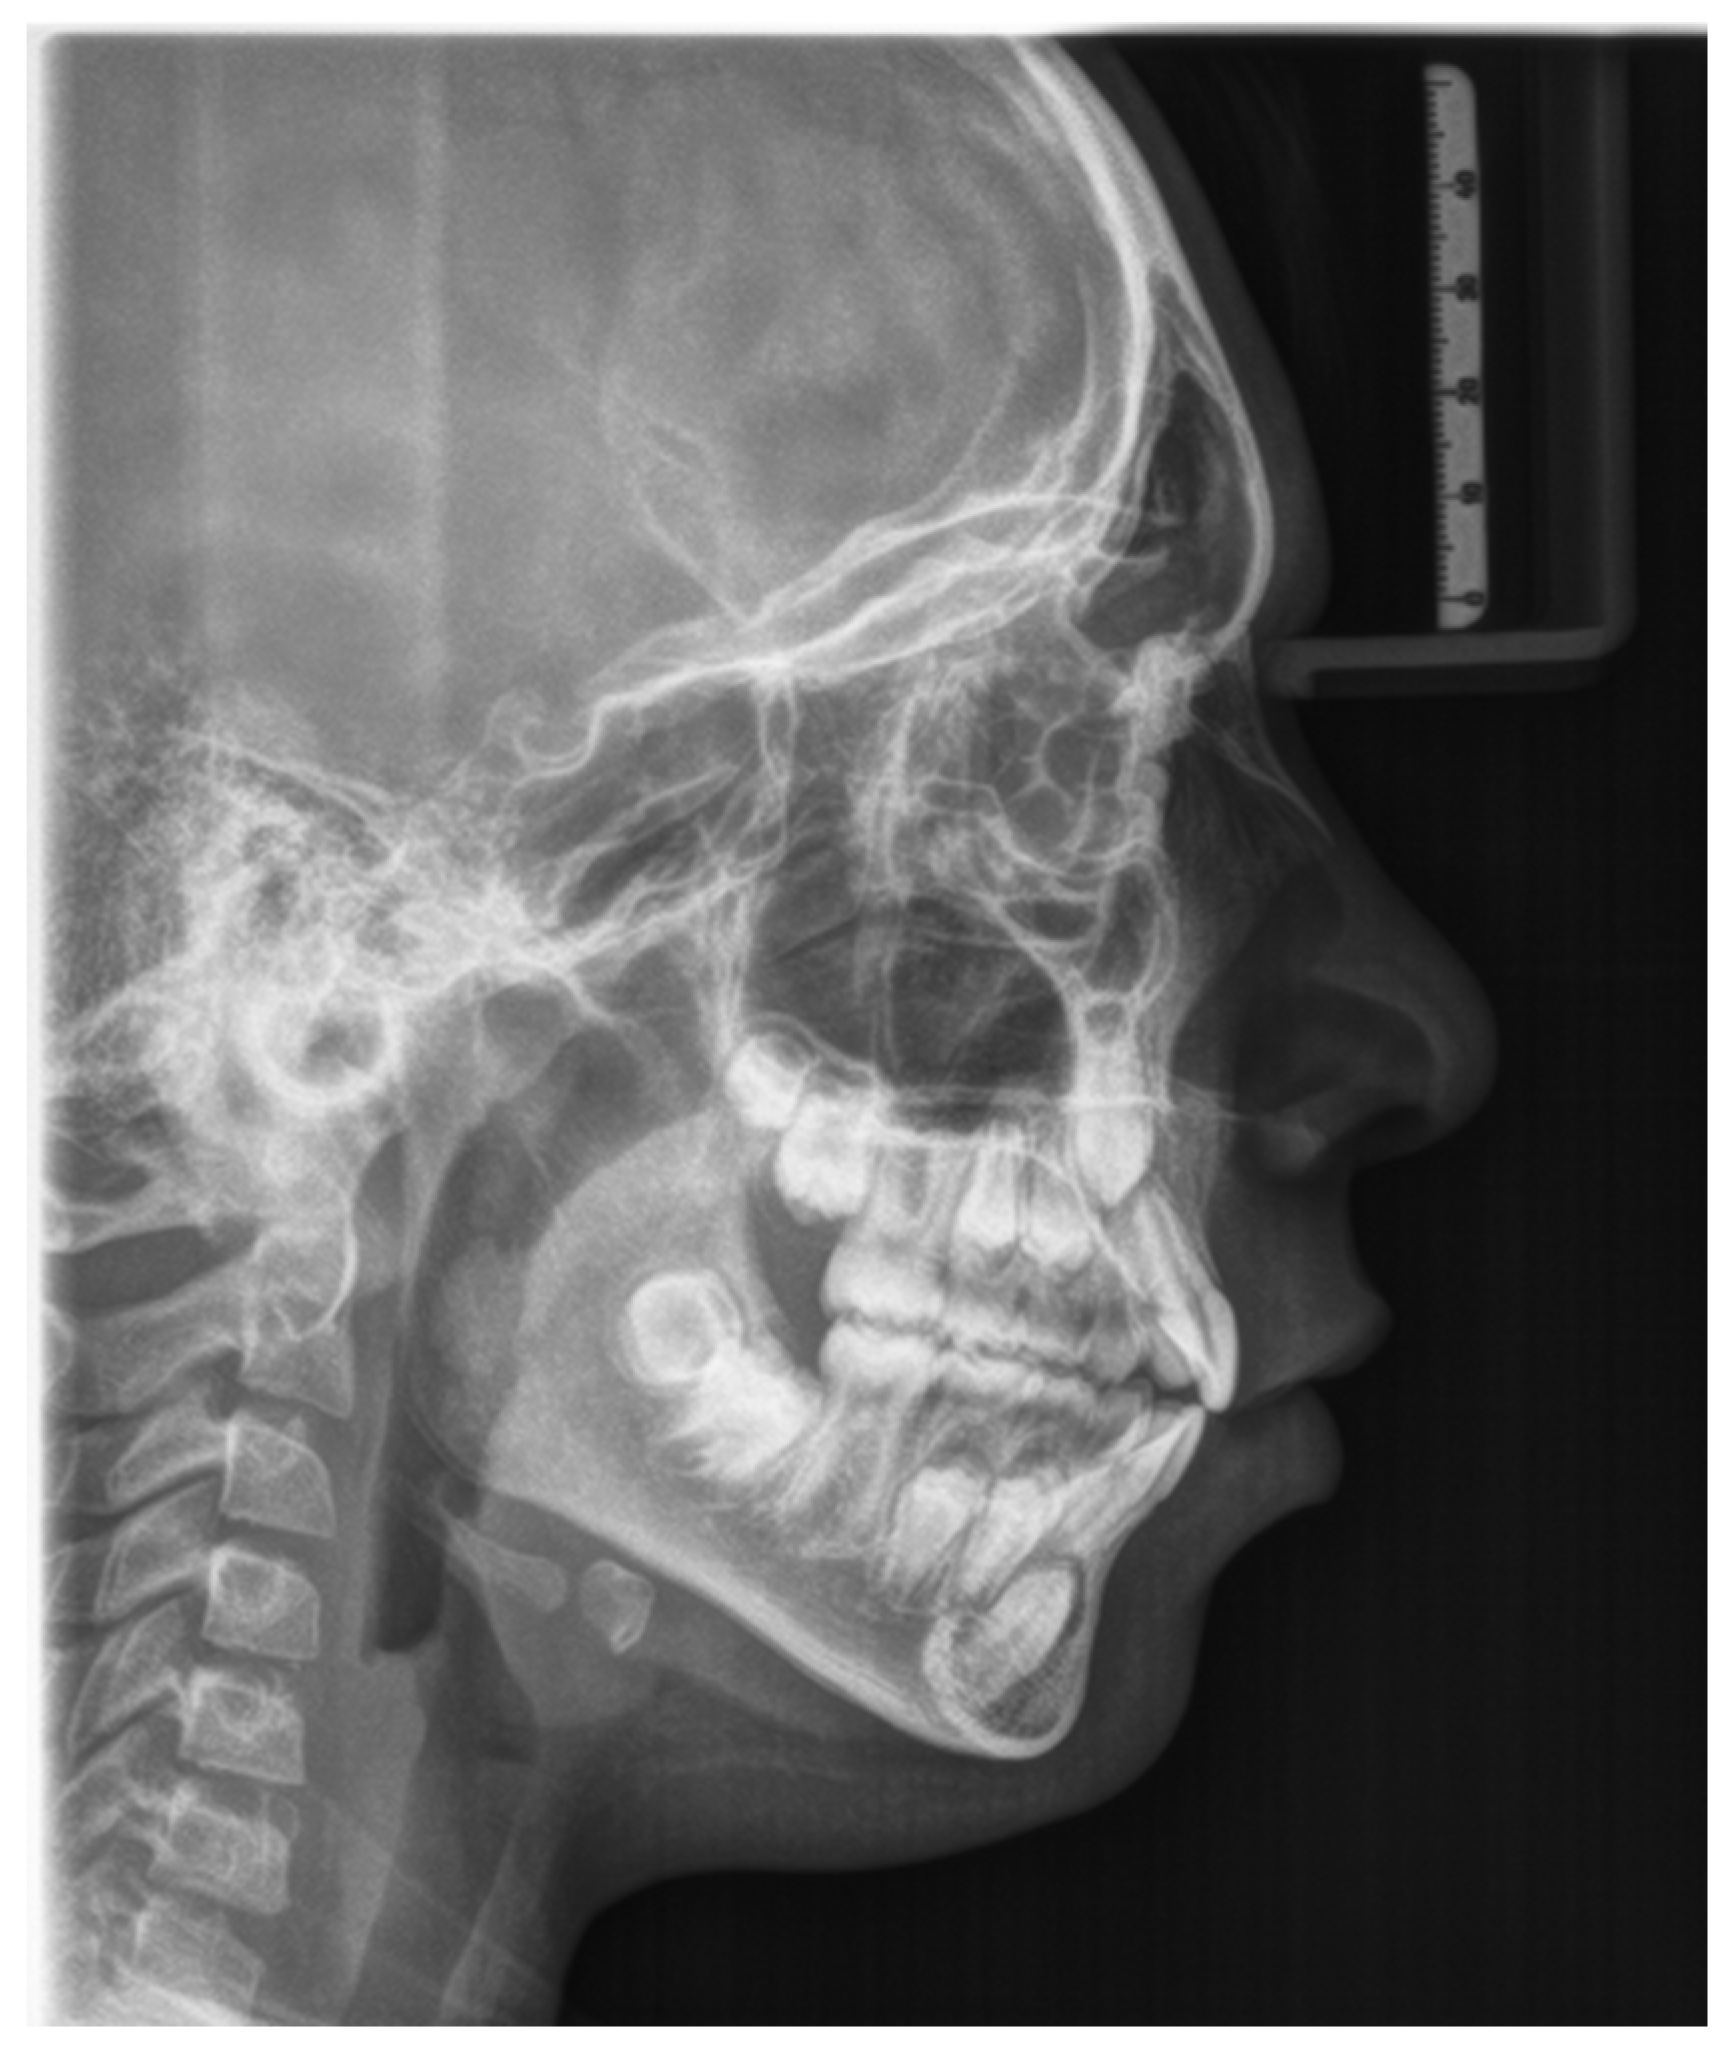

| Measure | Value | Mean | Deviation | Measurement Analysis |

| Molar report (A6-B6) −1, N | −1.6 | −3 ± 3 | N | Class I dental |

| Overjet (B1-A1 Horz.) | 1.8 | 2.5 ± 2.5 | N | Normal |

| Overbite (B1-A1 Vert.) | 0.2 | 2.5 ± 2.5 | N | Normal |

| Inferior incisor extrusion (B1-Occl.) | 0.5 | 1.25 ± 2 | N | Normal |

| Angolo Interincisivo (A1-B1 angle) | 118.2 | 132 ± 6 | -XX | |

| G02—Skeletal Reports | ||||

| Convexity (A-NPog) | 4.8 | 1 ± 2 | X | Class II bone |

| Lower face height (ANS-Xi-Pm) | 47.9° | 47 ± 4 | N | Facial meso |

| Dentoskeletal Ratios | ||||

| Upper molar position | 12.1 | 17 ± 3 | -X | Class III |

| Inferior incisor protrusion (B1-APog) | 3.7 | 1 ± 2.3 | X | Protrusion |

| Superior incisor protrusion (A1-APog) | 5.5 | 3.5 ± 2.3 | N | Normal |

| Lower incisor inclination | 30.5° | 22 ± 4 | XX | |

| Upper incisor inclination | 31.3° | 28 ± 4 | N | Normal |

| Occlusal plane inclination | 19.9° | 24.5 ± 4 | -X | |

| Craniofacial Reports | ||||

| Facial depth (PoOr-NPog) | 81.7° | 88.5 ± 3 | -XX | Facial dolic |

| Facial axis (BaN-PTGn) | 86.5° | 90 ± 3 | -X | Facial dolic |

| With facial icity | 68.4° | 68 ± 3.5 | N | Facial meso |

| Mandibular plane angle (GocMe-P) | 29.9° | 24.5 ± 4 | X | Facial dolic |

| Jaw depth (PoOr-NA) | 86.8° | 90 ± 3 | -X | Retrognathia |

| Palatal floor (PoOr-ANSPNS) | 0.3° | 1 ± 3.5 | N |